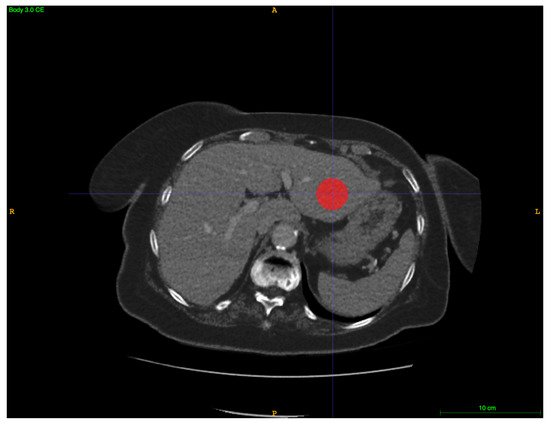

2.2. CT Imaging and Volumetry

2.3. Image Postprocessing